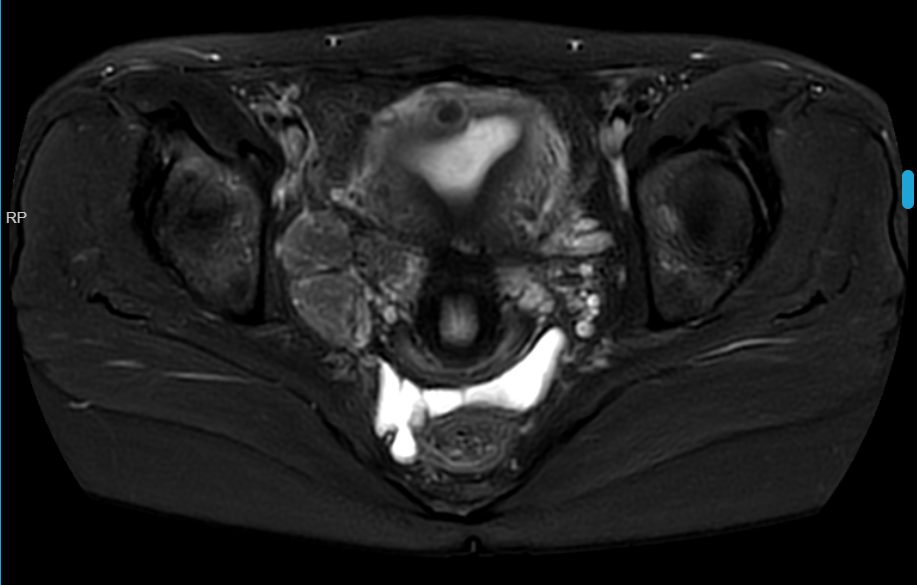

盆腔磁共振平扫+增强扫描:

影像所见:子宫表面欠光整,肌层、浆膜下见多发点状、结节状T1低信号,T2稍低信号,边界清楚,大者长径约14.5mm,不均匀强化。右侧盆腔见三枚T1低信号T2稍高混杂信号,增强明显较均匀强化,边缘光整,大者约23.3mm*38mm。

MRI提示:

1.子宫多发肌瘤;

2.右侧盆腔多发异常信号,考虑良性肿瘤可能,请结合临床。